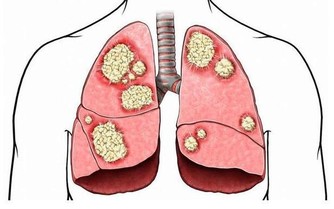

最後也是重中之重就是當發現誤吸入了汞氣體後,必須趕緊去醫院做詳細的檢查。